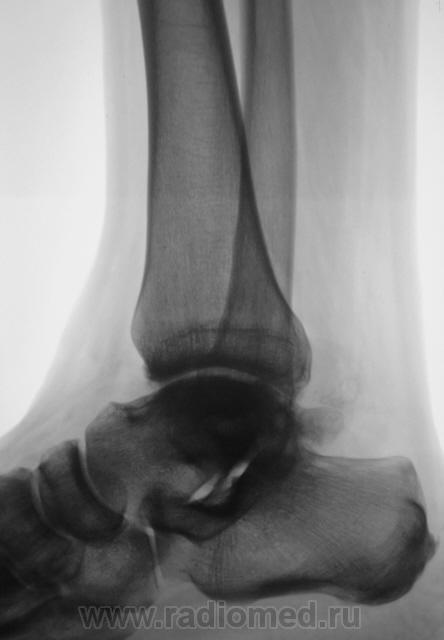

Пациент направлен на рентгенографию голеностопного сустава с диагнозом ДОА.

После внутрисуставного перелома вероятность доа оччень высока. Колгда была травма?

Травма была два года тому.

Похоже  на  остеохондропатию  блока  таранной  кости  +   ДОА.

А присутствует линейный (или лентовидный, я их путаю) остеопороз, а это признак острого процесса.

Будем думать, что некроз блока таранной кости не такой уж и асептический, какая-то инхвекция там есть.

Посттравматический артроз с кистовидной перестройкойлатерального мыщелка Субхондральное уплотнение исужение суст. щелей естьИ неконгруэнтность большеберцового эпифиза к таранной маленько просматривается?